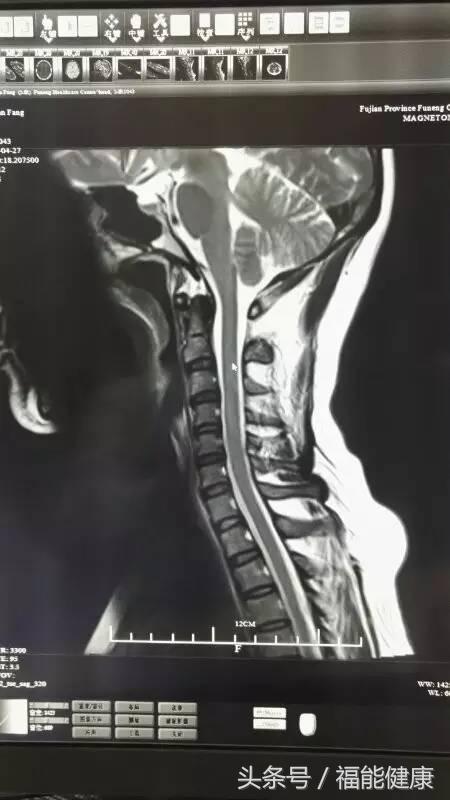

据福能健康管理中心放射影像科主任郑章和介绍,核磁共振对脑、甲状腺、肝、胆、脾、肾、胰、肾上腺、子宫、卵巢、前列腺等实质器官以及心脏和大血管以及骨关节都有很好的诊断功能。核磁共振的原理实际上是,将人体置于特殊的磁场中,用无线电射频脉冲激发人体内氢原子核,引起氢原子核共振,并吸收能量。在停止射频脉冲后,氢原子核按特定频率发出射电信号,并将吸收的能量释放出来,被体外的接受器收录,经电子计算机处理获得图像,这就是核磁共振成像的基本原理。

郑主任谈到,许多人对核磁共振检查的认识是有误区的。实际上,核磁共振是磁场成像,没有放射性,对人体无害,非常安全,这是核磁共振的优势之一。此外,核磁共振在发现病变及发现肿瘤方面也是一把好手,与其他辅助检查手段相比,核磁共振具有成像参数多、扫描速度快、组织分辨率高和图像更清晰等优点。

核磁共振检查不仅可以早期发现某些肿瘤、脑梗塞、脑出血、脑脓肿、脑囊虫症及先天性脑血管畸形,还能确定脑积水的种类及原因等。通过对头部及心脏等部位的核磁检查,在身体健康尚未发出红灯警讯前,早期发现心脏病、脑梗等高风险疾病隐患。当然,MR检查也不是万能的,在很多情况下也需要结合DR、超声、CT等手段,互为补充。同时,在诊断疾病的时候,尚需要密切结合临床其他资料。